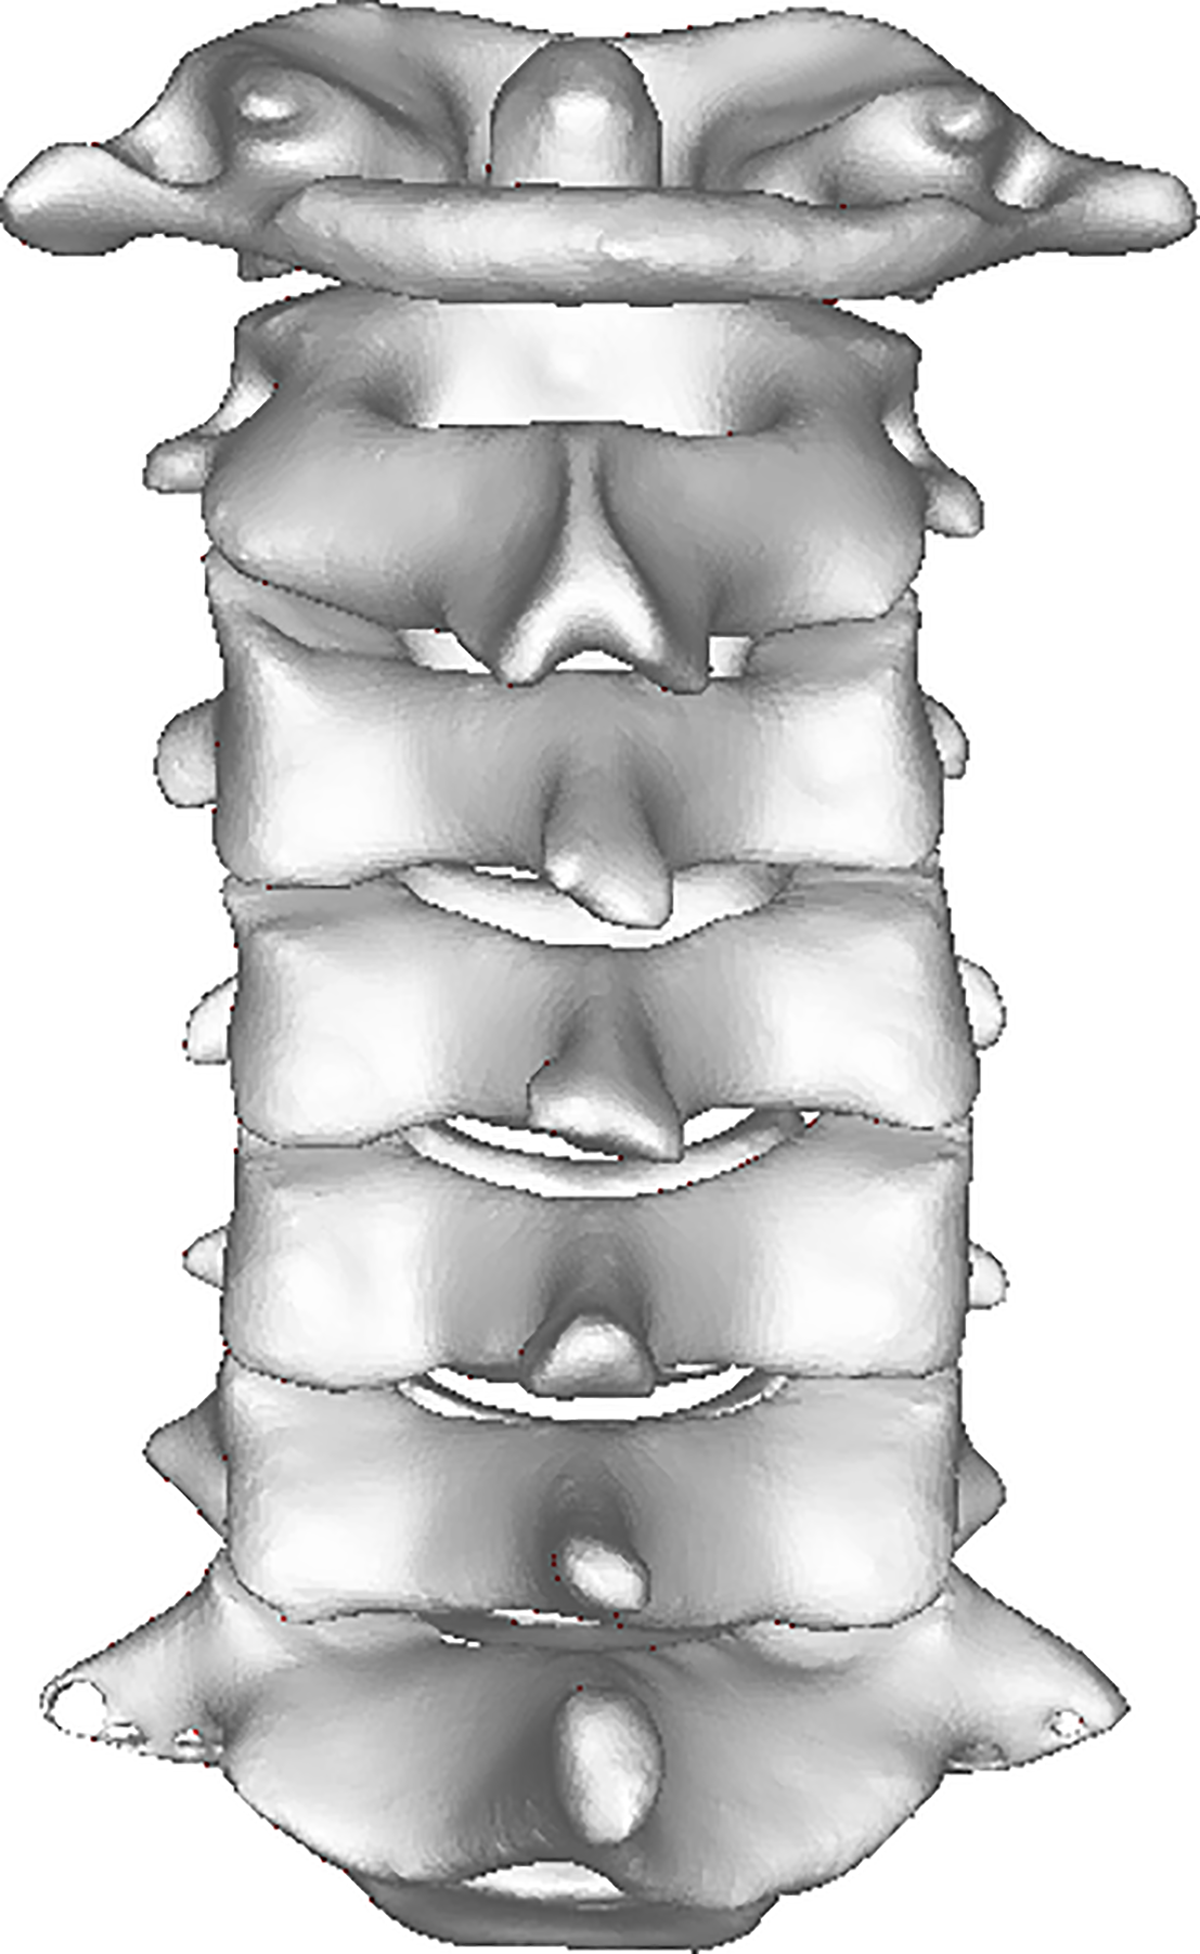

Normal lumbar spine phantom with healthy vertebral bodies, intact discs, spinal canal, and nerve roots